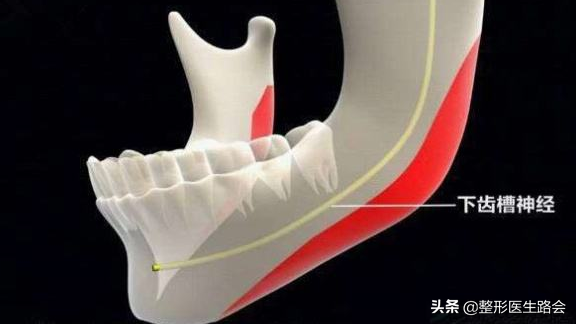

截多截少是根據(jù)術(shù)前的周密檢查、如何在不傷神經(jīng)的前提下進(jìn)行,有些求美者檢查片子一出來(lái),神經(jīng)線低,那么截取骨量必然會(huì)少。

下頜角神經(jīng)線